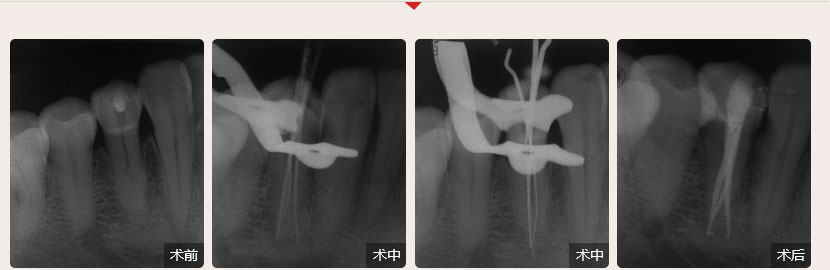

德倫口腔醫(yī)生全國(guó)根管治療技術(shù)競(jìng)賽獲獎(jiǎng)案例展示